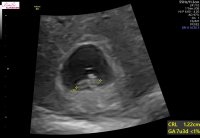

hjertet banket og vi fikk til og med et lite hopp. Målte helt riktig til hvor langt jeg var